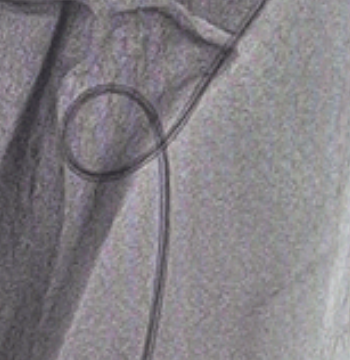

图2 以PTCA导丝通过弯曲

泥鳅导丝怎么用新心联播|卢竞前:桡动脉入路困难的处理方法_https://www.jmylbn.com_新闻资讯_第9张